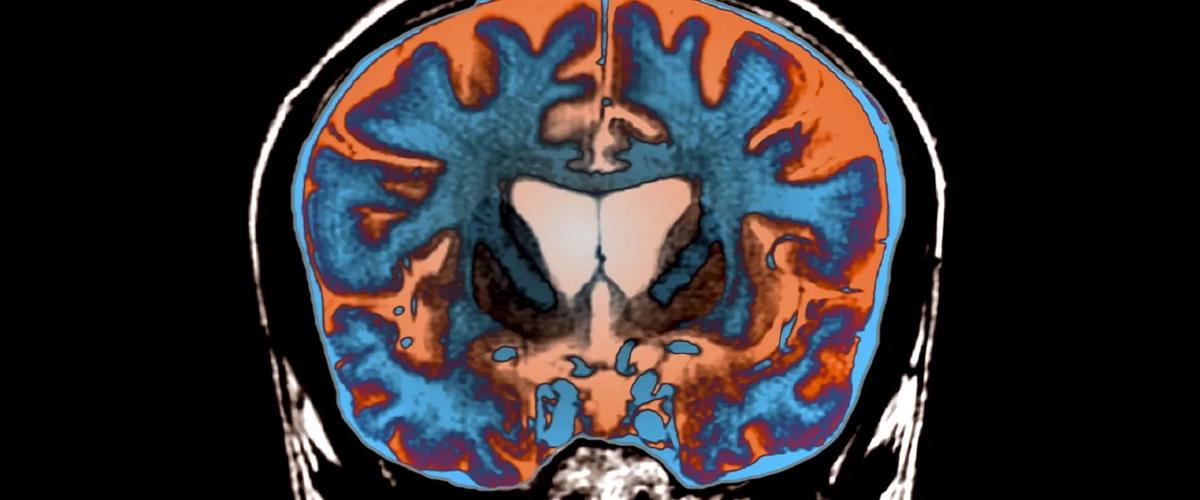

Болезнь Хантингтона — это тяжелое нейродегенеративное заболевание, вызванное мутацией в гене HTT, которое приводит к синтезу аномально крупных белков под названием хантингтины. Эти белки склонны накапливаться внутри клеток, что вызывает их повреждение. Однако до сих пор не было ясно, почему из-за этого погибают нервные клетки.